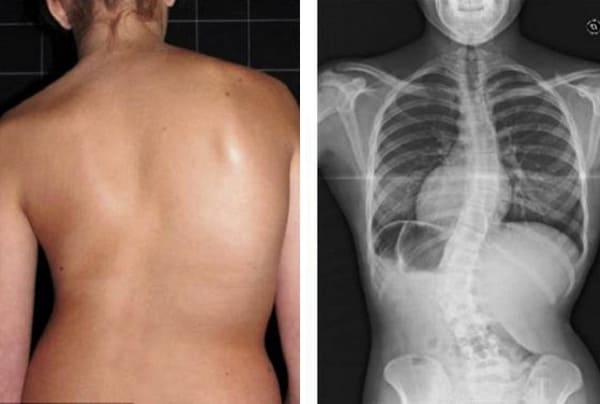

Mire estas fotografías. Esto es lo que les sucedió a todos los que ignoraron los síntomas. Hoy, estas personas están completamente sin esperanza, y muchos de ellos no tienen a quién acudir en busca de ayuda. ¿Realmente, quiere un destino así?

Mujer de 52 años. Desplazamiento y deformación severa del disco intervertebral, compresión de los nervios y daño a la médula espinal.

"Joroba de viuda" — deformación de las vértebras y dolor crónico, insoportable, que se intensifica cada día.

Hernia de disco intervertebral, compresión de los nervios, pérdida de sensibilidad y parálisis parcial de las piernas.

Mujer, 62 años. Luxación grave de vértebras. Hondrodox restauró completamente la columna en 2 cursos.

Mujer, 42 años. Deformación severa de la articulación de la rodilla, rodillas cóncavas. El curso de Hondrodox requirió 2 cursos para la recuperación completa.

Hombre, 37 años. Corrección completa de la postura con Hondrodox en 1 curso.

Mujer, 51 años. Joroba de viuda y deformación de la columna. Eliminación completa de la joroba tras 1 curso de Hondrodox.